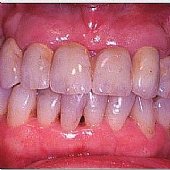

• Geschliffene Zähne in Kombination mit Implantaten.

• Die fertige Versorgung - mit stark individualisierten Zähnen kann man ein möglichst natürliches Ergebnis erzielen.